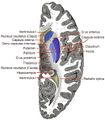

رسم توضيحي لمسار ألياف lemniscus; medial lemniscus بالأزرق, lateral بالأحمر. | ||